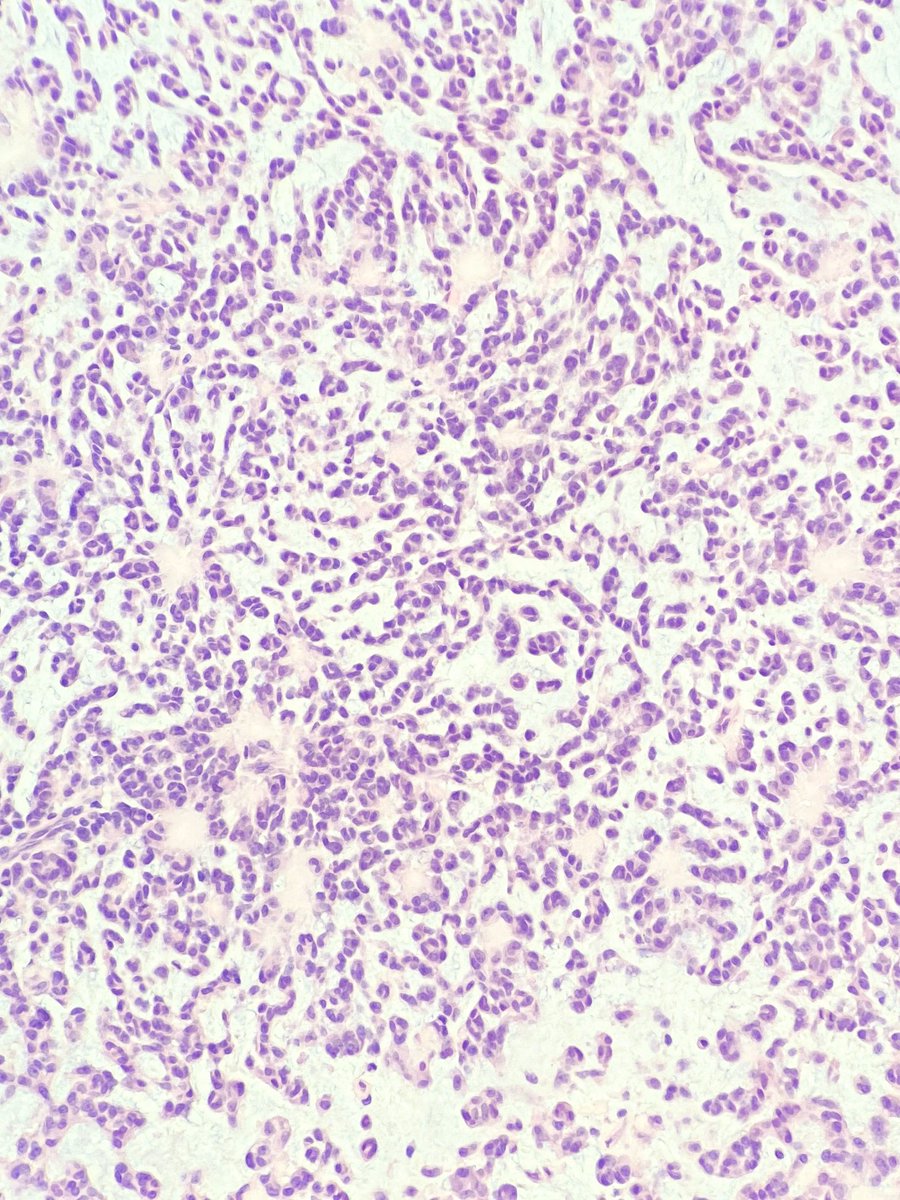

It's beautiful when tumors read the book. Gastric body mass. When autoimmune gastritis meets well-differentiated NET.

#GIpath#pathology pic.twitter.com/67Qbxob19d